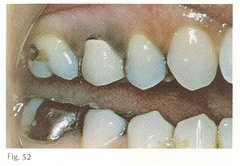

periapical abscess

-Pain, swelling, fistula, slight extrusion of tooth at root -radiographically thickening of PDL and periapical radiolucency ACUTE